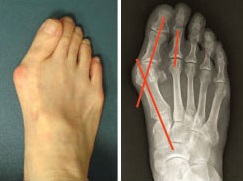

Radiografía

En la proyección dorsoplantar se observan claramente el primer metatarsiano varo y la desviación lateral de los huesos sesamoideos. Puede medirse el ángulo entre el primer y segundo metatarsianos. En la proyección de perfil se evalúa el estado de las articulaciones metatarsofalángica y cuneo-metatarsiana.